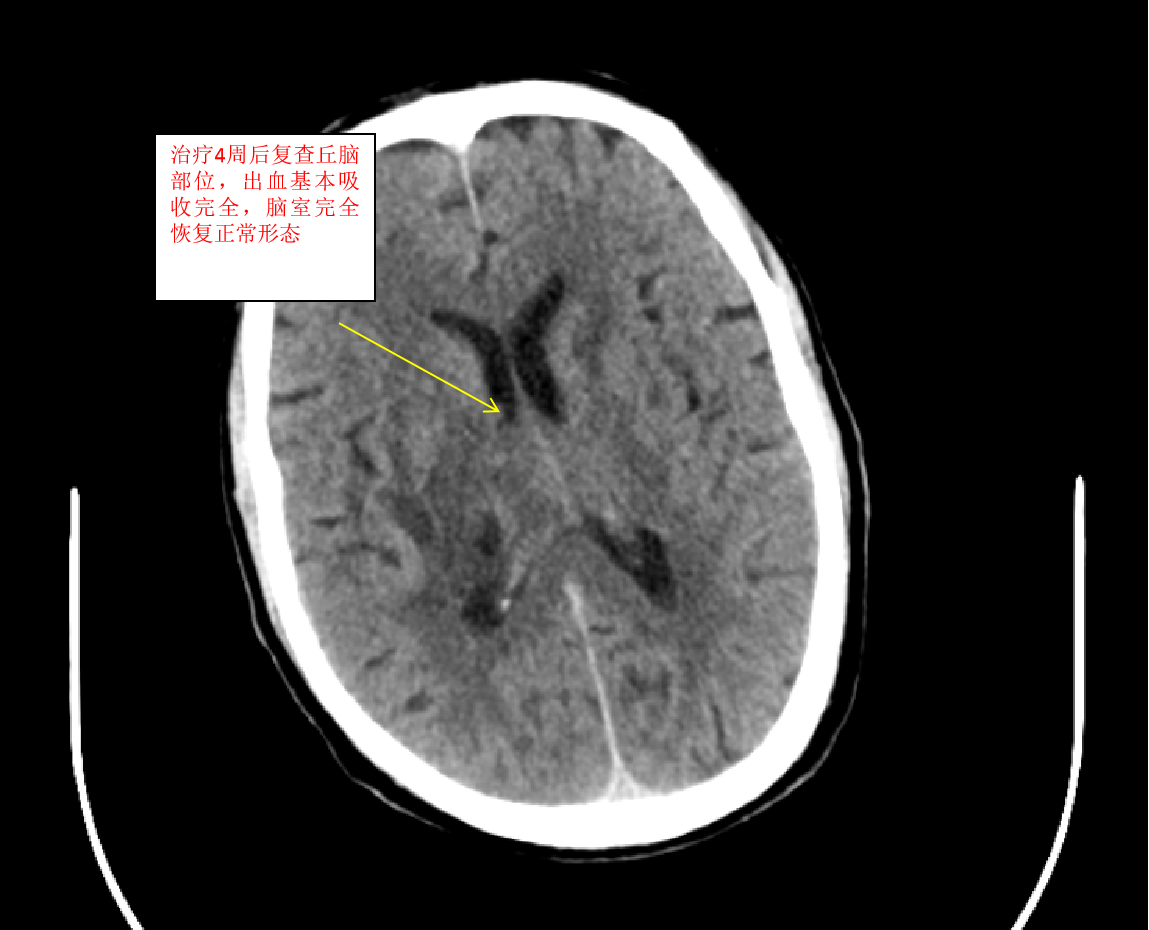

我们收到此病人后,立即给予术前准备,并在局麻下行双侧脑室外引流术,由于病人脑室有大量出血,穿刺置管有很大的技巧,因为大量的脑室出血,致脑室铸型,打乱了正常的解剖结构,穿刺失败的可能性很大。经术后复查颅脑CT,发现右侧管道引流较通畅,决定拔除左侧引流管,并通过右侧引流管给予尿激酶注入反复溶解血块并引流出血性液体,共应用尿激酶10次,每日一次,为了预防感染,并在每次冲洗时给予严格换药。于第10天经复查颅脑CT发现脑室出血已基本清除,决定给予拔除脑室引流管。为了放出残留血性脑脊液,尽量廓清病人脑脊液,于拔管后第二天开始给予腰穿,共进行腰穿10次,每日一次,腰穿时尽量多放出脑脊液,才能取得更好的效果。于近日复查颅脑CT发现丘脑出血已完全吸收,脑室积血已完全清除,未出现脑积水,未出现颅内感染。经过这段时间的治疗后病人的意识状况已明显好转,由深昏迷转为神志恍惚,肢体的偏瘫也逐渐好转,目前仍给予肢体康复训练治疗,几天后就能治愈出院。